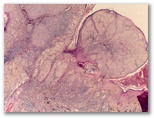

¿Queratosis seborreica?

Diagnostico